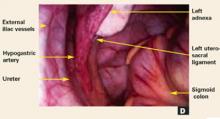

FIGURE 1D Inner concentric circle

Laparoscopic procedures. It may sometimes be appropriate to perform surgical therapy during a pelvic evaluation. For example, most ectopic pregnancies can be treated laparoscopically, as can many cases of endometriosis. It is desirable, however, to complete the pelvic examination before performing any subsequent procedures, including the removal of ovarian cysts, ovaries, fibroids, or the uterus, since blood and peritoneal trauma may make abnormal findings difficult to perceive.